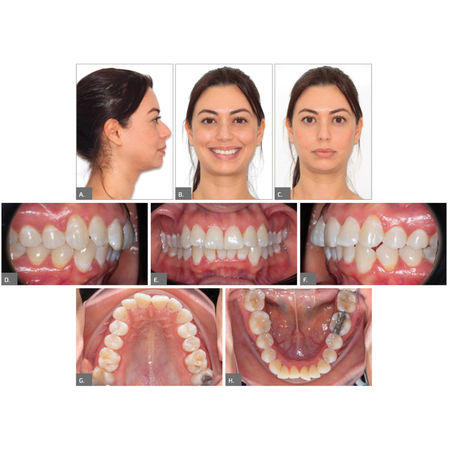

Orthodontic-surgical treatment of skeletal Class II malocclusion using aligners

OBJECTIVE: To describe the clinical management of a patient with skeletal and dental Class II malocclusion, presenting with snoring as the chief complaint and secondary concerns related to facial profile and smile aesthetics. CASE REPORT...

aesthetics Malocclusion Surgery Snoring Aligners